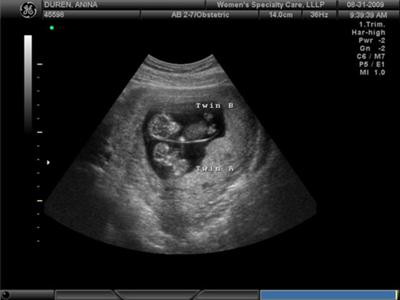

W przypadku ciąży bliźniaczej (lub potrójnej) rozwój każdego dziecka jest mniej więcej taki sam, jak w przypadku ciąży singleton. W tym samym czasie mali mężczyźni mogą zauważalnie (o kilka milimetrów) różnić się wzrostem. To całkiem normalne.

Zdjęcie USG: